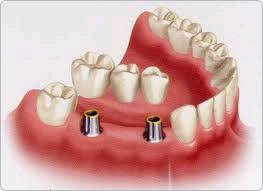

By way the best way of replacing teeth is using implants. Implants can support many teeth, maintain bone levels and being fixed are a natural way of replacement.

Implants are made from Titanium alloy, are bio-inert and have been used in dentistry for over 50 years.

2 weeks later a metal porcelain bridge was attached to the implants by way of integral implant screws. patient was very happy to be able to chew on both sides; now he is considering Invisalign.